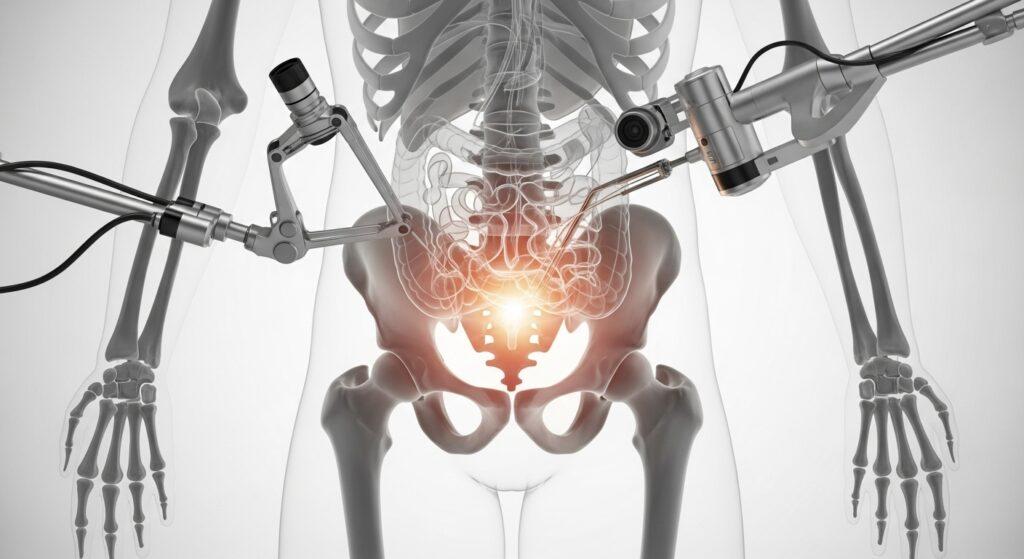

3. Anatomía y características individuales

La anatomía de cada persona puede influir en la viabilidad técnica de la cirugía robótica. Factores como cirugías previas, variaciones anatómicas o condiciones específicas de la región a intervenir pueden determinar si esta técnica es recomendable.

No todos los procedimientos requieren tecnología robótica. Esta técnica se recomienda principalmente en intervenciones que demandan alta precisión, como cirugías prostáticas, renales complejas o reconstructivas. Tu diagnóstico influye directamente en si esta opción es viable para ti.